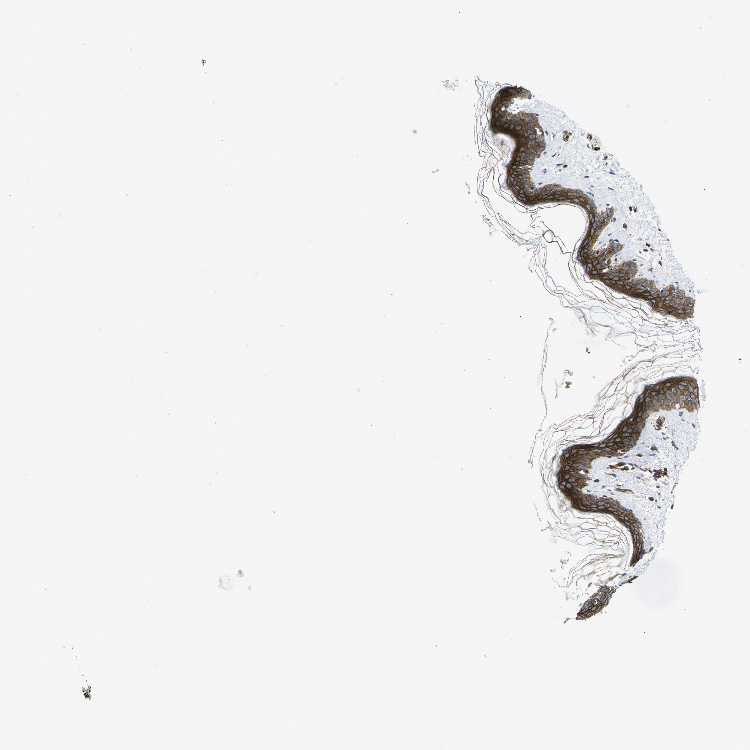

SKIN 1 - Antibody stainingi

Antibody staining in the annotated cell types in the current human tissue is reported as not detected, low, medium, or high, based on conventional immunohistochemistry profiling in selected tissues. This score is based on the combination of the staining intensity and fraction of stained cells.

Each image is clickable and will lead to virtual microscopy that enables deeper exploration of all samples and also displays staining intensity scores, fraction scores and subcellular localization as well as patient and tissue information for each sample.

Antibody HPA014055Antibody CAB013302

Langerhans Medium-

Cells in basal layer -High

Cells in corneal layer -Not detected

Cells in granular layer -High

Cells in spinous layer -High

Endothelial cells -High

Extracellular matrix -Not detected

Fibroblasts Low-

Fibrohistiocytic cells -High

Keratinocytes Medium-

Langerhans cells -High

Lymphocytes -High

Melanocytes MediumHigh

Vascular mural cells -High